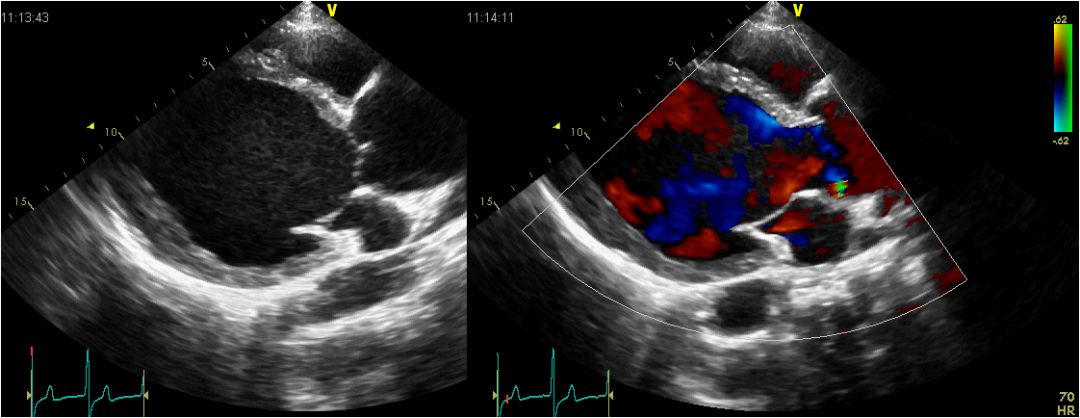

超声心动图:双平面法LVEF48%,左心室心尖部、后壁中下部运动减弱,心尖部变薄)。左心室增大。轻度二尖瓣关闭不全,左冠状动脉7.5mm, 右冠状动脉8mm